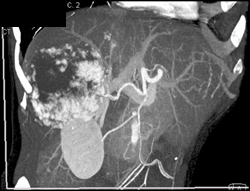

Cholangiocarcinoma